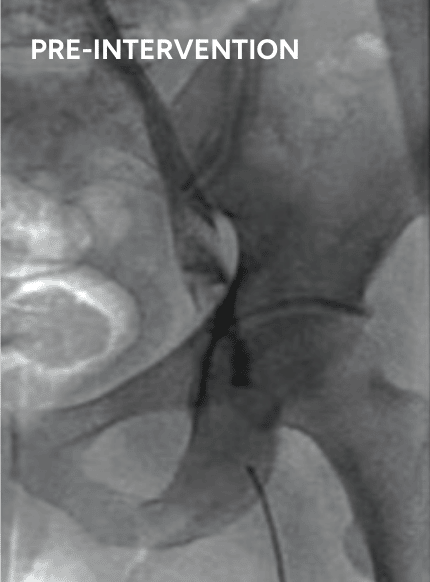

4.

Venogram of axillary and subclavian vein

Total of 12mg of r-tPA